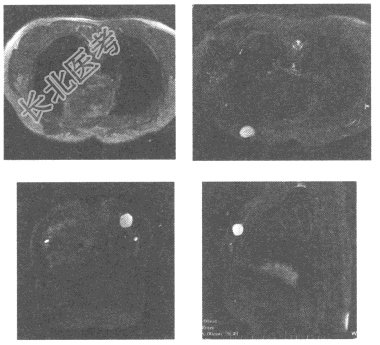

- 单项选择题女,40岁, 乳腺MRI平扫见左侧乳腺类圆形明显长T2信号灶,图像如下, 最可能的诊断为

A、乳腺腺病

B、乳腺癌

C、乳腺纤维腺瘤

D、乳腺脓肿

E、乳腺囊肿